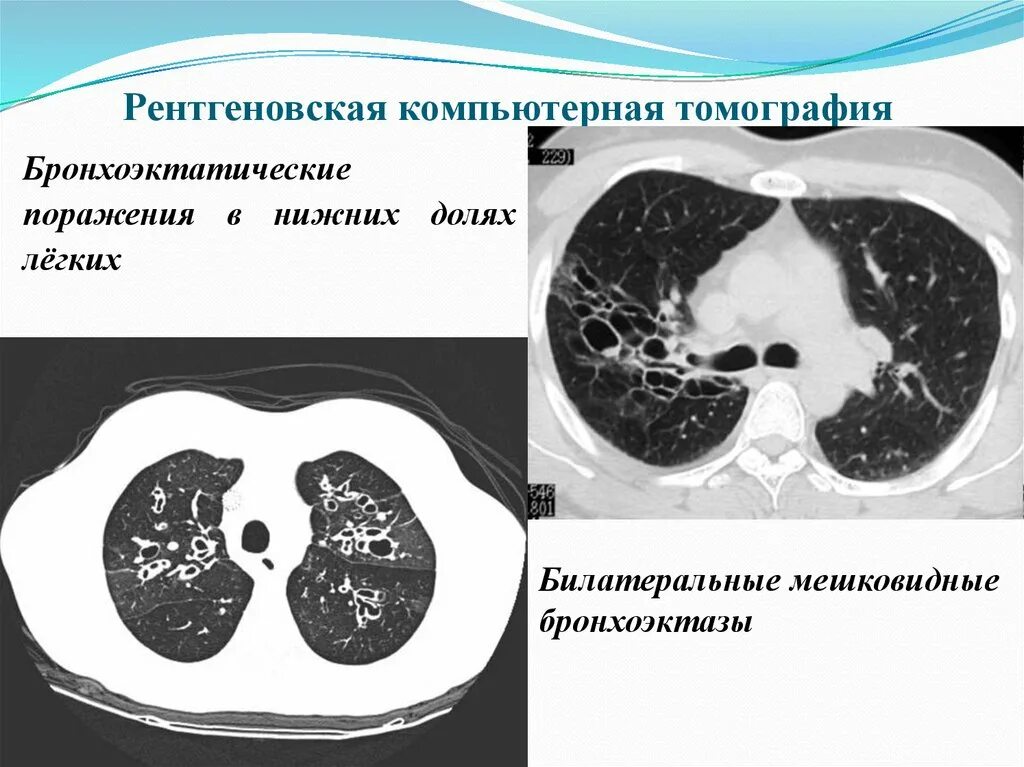

Заболевание кт